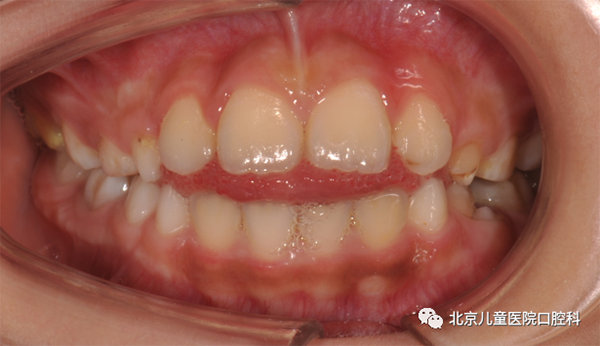

图1 舌习惯引起的前牙局部开合

图2 舌习惯引起的前牙反合